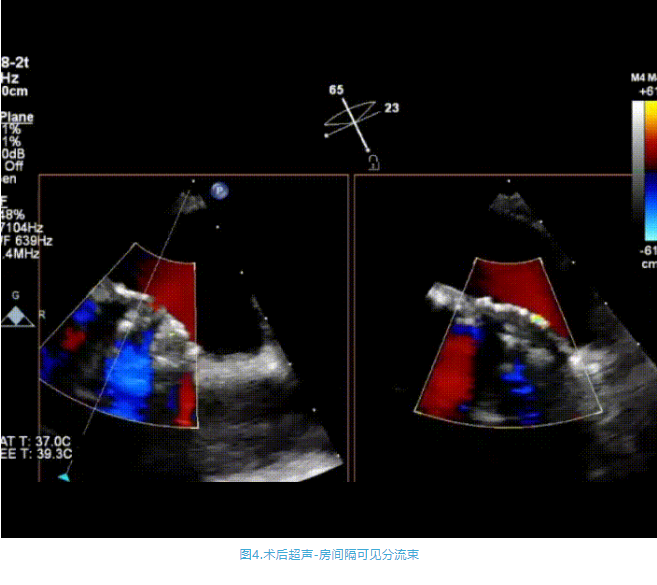

術中首先在局麻下穿刺股動脈、股靜脈,完成心導管檢查評估后轉為全麻,在食道超聲引導下穿刺房間隔,穿刺成功后將加硬導絲送入左上肺靜脈建立軌道,根據患者病情行球囊預擴張后植入6mm孔徑房間隔造孔支架,經透視及食道超聲評估支架左右盤展開良好,夾持于房間隔兩側,固定穩定、位置良好,食道彩超顯示房水平右向左為主分流,分流孔直徑符合預期大小,心導管檢查評估達到預期效果,釋放造孔支架。術后12h患者下床活動,恢復順利,擬于近日完善術后評估后出院。

心房分流術是通過器械制造穩定可控的心房間分流,適應證包括藥物治療效果不佳的左心衰或肺動脈高壓右心衰。本例患者為肺動脈高壓右心衰,術中成功放置MicroFlux®造孔支架在房間隔理想位置上,創造穩定可控的心房間分流(此例患者以右向左分流為主),在不顯著增加左心負擔的情況下,有效降低患者右心房壓力、緩解體循環淤血,增加左心輸出量,改善患者癥狀、活動耐力和生存質量。同時,國內外也已經開展多項房間隔造孔支架在射血分數保留、射血分數中間值和射血分數降低的左心衰患者中的臨床研究,結果顯示對于經過充分的規范化藥物治療后仍控制不佳的患者,心房分流術可改善患者的癥狀及生存質量。